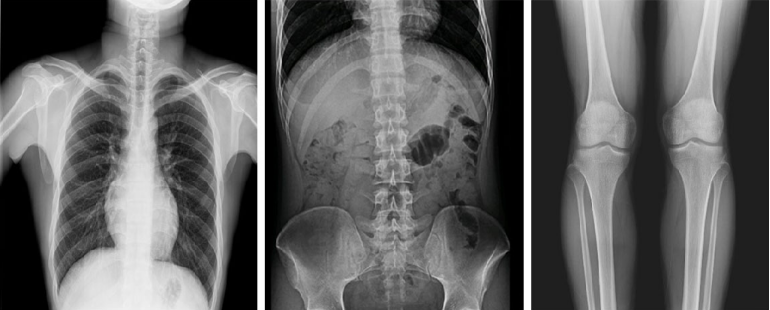

而且,影像采集幅面大,17×17英寸超大視野可覆蓋成年人的全胸全腹,并且能在連續(xù)動態(tài)中實時高清點片,從而達到精準診斷的目的。設備靈活高效的多維度運動設計,也帶來了更加智能化、人性化操作體驗,可大幅提升檢查效率。

與此同時,普利德動態(tài)平板DRF還具有全身拼接功能,尤其適用于全脊柱和全下肢攝影,為臨床提供高精度圖像,輔助脊柱畸形矯形治療、康復檢查。